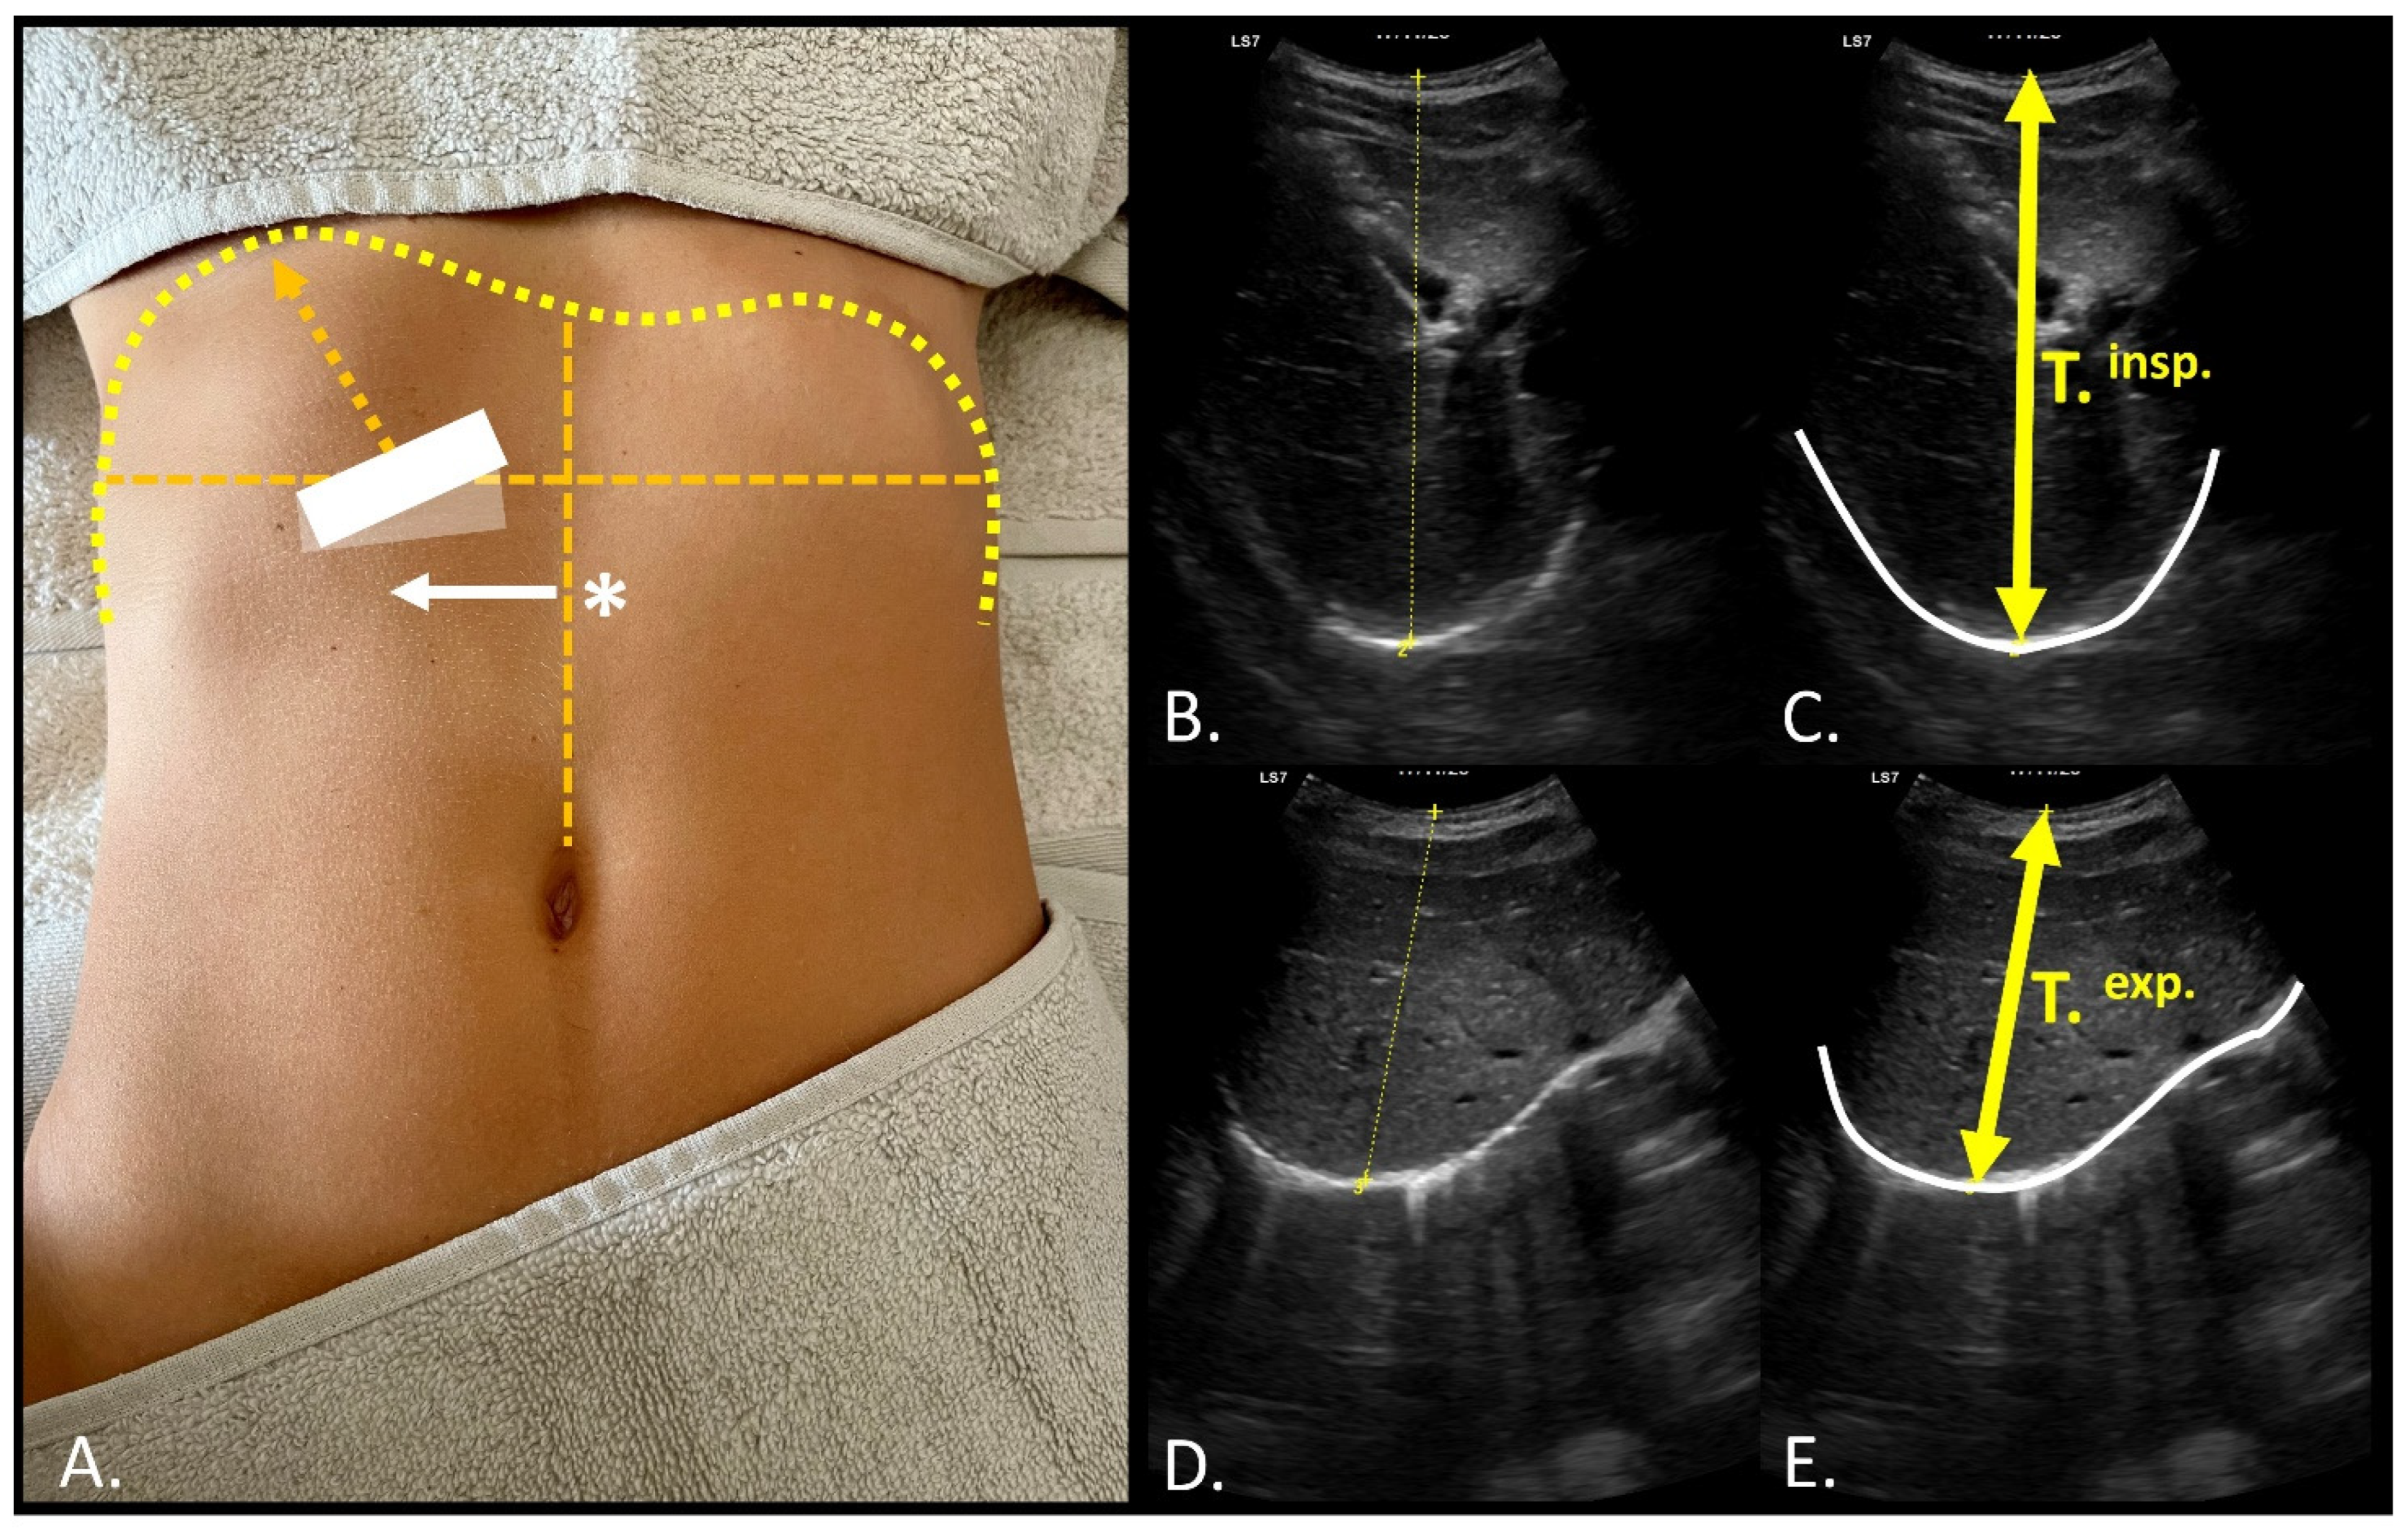

2.4. Sonographic Measurements